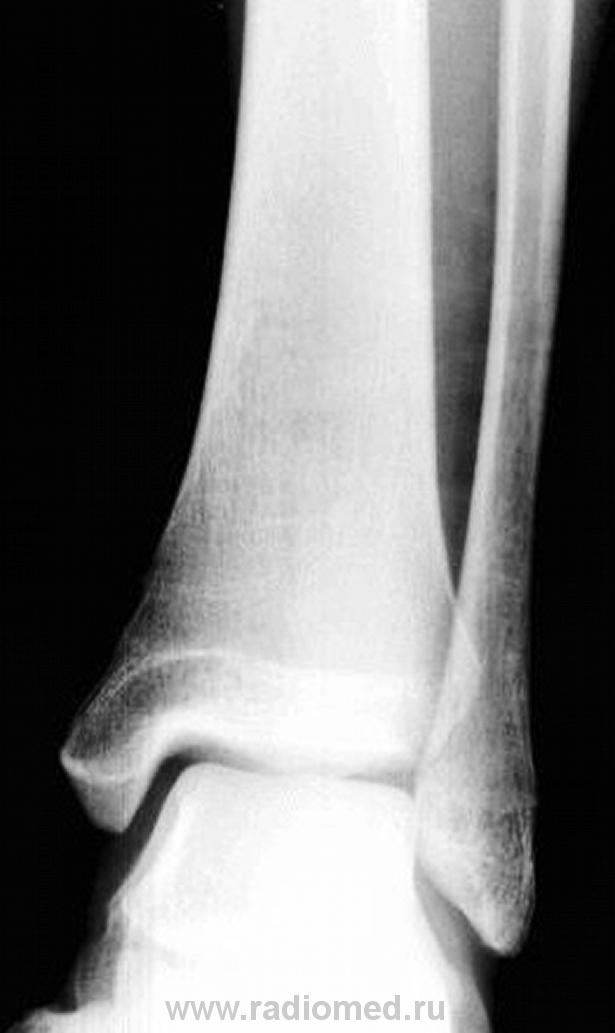

А как на счет малоберцовой кости ? Не было ли тут небольшого переломчика?

киста пяточной кости и вальгусная деформация голеностопного сустава

По поводу вальгусной деформации, а не в укладке ли дело?

Мы довольно часто встречаемся с такой патологией - костная киста, при проведении экспертизы годности к военной службе, при рентгенометрии "продольного плоскостопия", и довольно часто это патологическое состояние бывает с одной стороны.